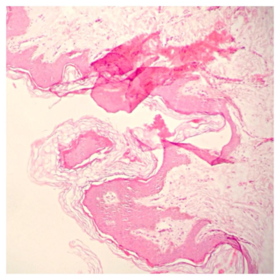

Láminas de Histología

Description

Laboratorio de histología, Bibliografía Ross Pawlina 5ta Edición.